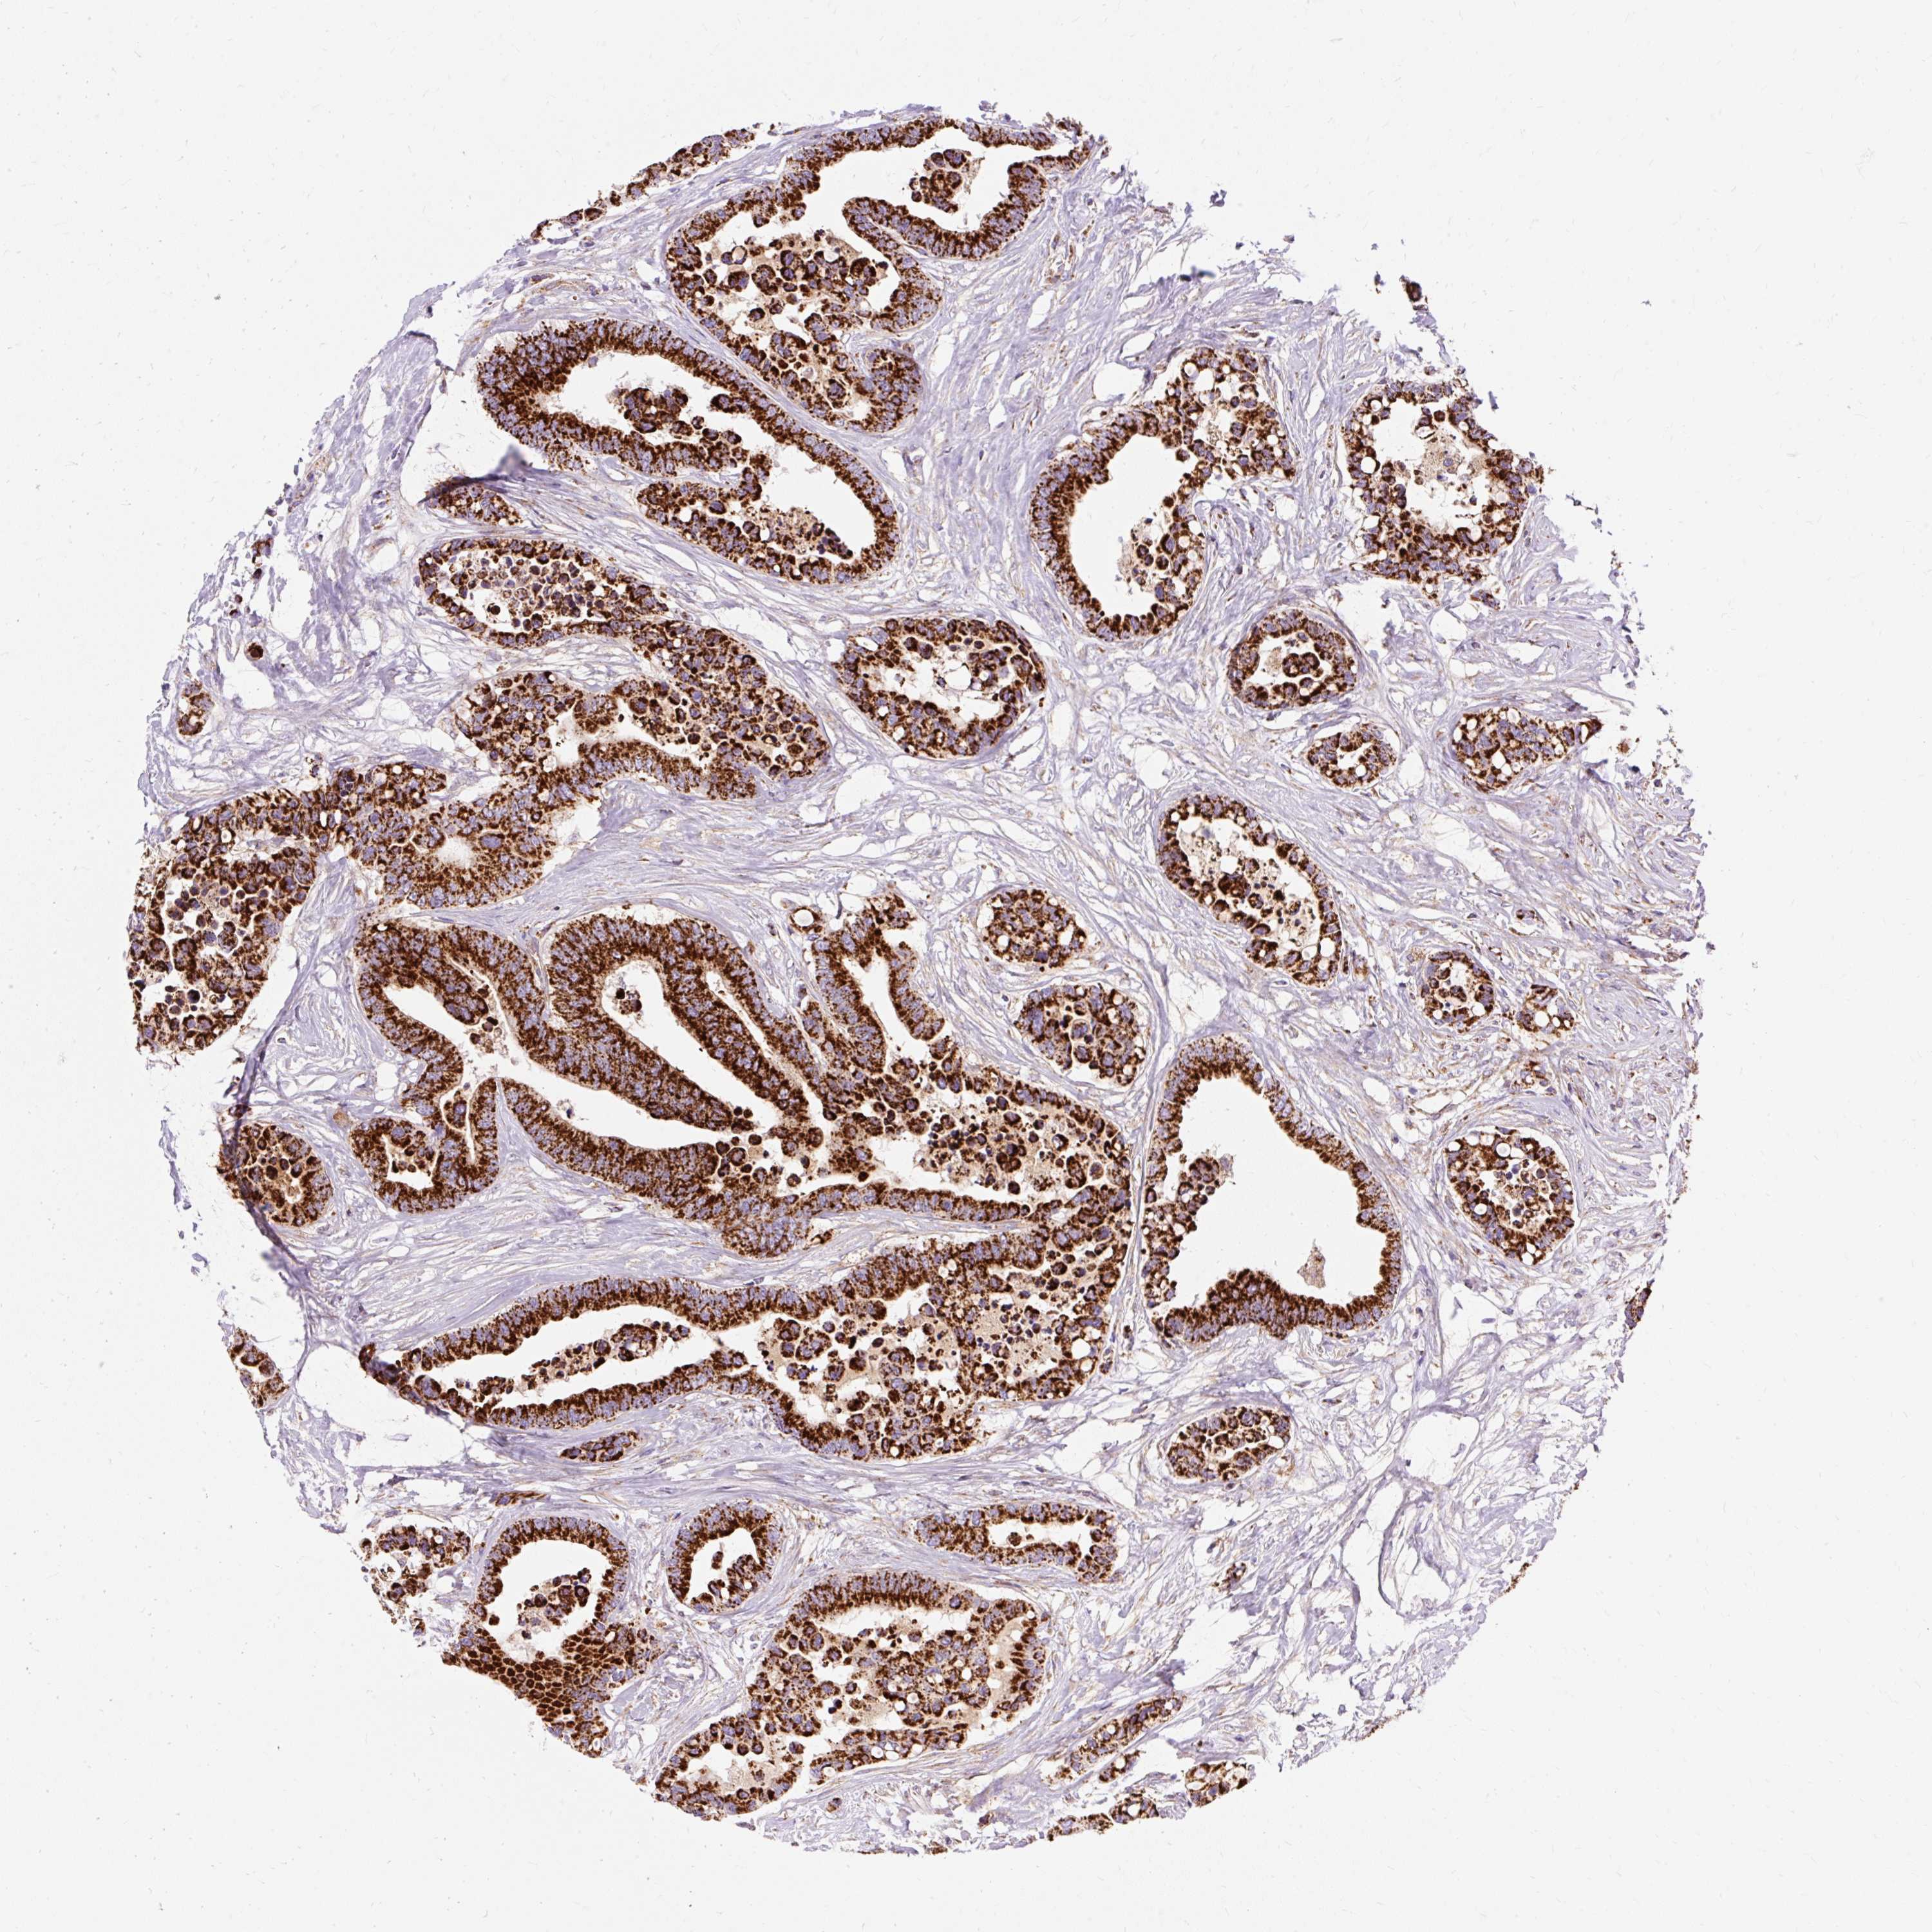

CANCER COLORECTAL CANCER Show tissue menu

Colorectal cancer

Human cancer

Colon adenocarcinoma